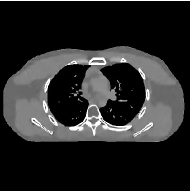

This section compares the reconstruction quality and runtime among the proposed MBIR method, PWLS-ST-, and other three MBIR methods, PWLS-EP, PWLS-DL, and PWLS-ST-. Table I shows that, for both 2D and 3D sparse-view CT reconstructions of the XCAT phantom, the proposed PWLS-ST- model outperforms PWLS-EP and PWLS-ST- in terms of RMSE. In addition, PWLS-ST- using a square transform (of size ) achieves lower RMSE than PWLS-DL using an overcomplete dictionary (of size ) for 2D sparse-view reconstructions. Fig. 3(a) and Fig. 4 show the reconstructed images for 2D and 3D phantom experiments, with different reconstruction models and different number of views. (See the corresponding error maps in the supplement.) The proposed PWLS-ST- consistently gives more accurate image reconstructions compared to other MBIR methods. Specifically, PWLS-ST- has smaller errors in the heart region (see zoom-ins in Fig. 3(a)) of 2D reconstructions than PWLS-DL and PWLS-ST-. In addition, compared to PWLS-ST-, PWLS-DL and PWLS-ST- have some ringing artifacts around the edges with high transition, e.g., edges between air and soft tissues. (See a comparison of profiles of PWLS-ST- and PWLS-ST- in the supplement.) In particular, PWLS-ST- and PWLS-DL give more visible ringing artifacts for 2D reconstruction from fewer views, and PWLS-ST- has these ringing artifacts for 3D reconstructions regardless of the number of views (see zoom-ins in Fig. 4). Table II reports runtimes of different MBIR methods in reconstructing the -views XCAT phantom scan. (FBPConvNet is a non-MBIR method and its runtime for processing a image is approximately one second with a TITAN Xp GPU.) While providing better reconstruction quality, the proposed Algorithm 1 of PWLS-ST- has shorter runtime compared to the algorithms of PWLS-DL and PWLS-ST- in Section III-A. Similar to the PWLS-EP algorithm, the reconstruction time of the PWLS-DL, PWLS-ST-, and PWLS-ST- algorithms can be further reduced by using ordered subsets [51].

Fig. 3(b) shows that when tested on the clinical scan data, the proposed PWLS-ST- method improves reconstruction quality in terms of noise and artifacts removal (e.g., see zoom-ins for soft-issue regions), and edge preservation (e.g., see zoom-ins for bone regions), compared to PWLS-EP and PWLS-ST-. Compared to PWLS-DL, PWLS-ST- achieves comparable image quality, but requires less computational complexity.

| (a) 2D fan-beam CT experiments |